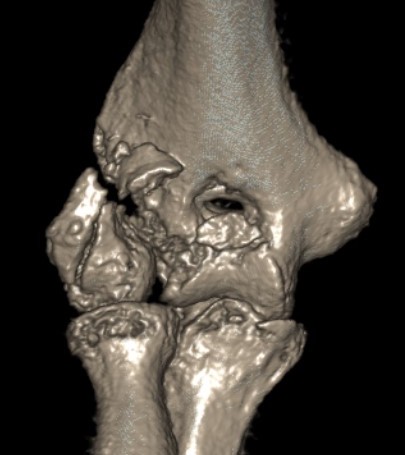

Dubberly Classification

| Type I | Type Ii | Type III |

|---|---|---|

|

Capitellar fracture

Capitellum + trochlea fracture In one piece Double arc sign seen on xray |

Capitellum + trochlea fractures In two separate pieces |